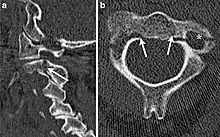

| CT scan of hangman's fracture | |

Hangman's fracture is the colloquial name given to a fracture of both pedicles, or partes interarticulares, of the axis vertebra (C2).[1]